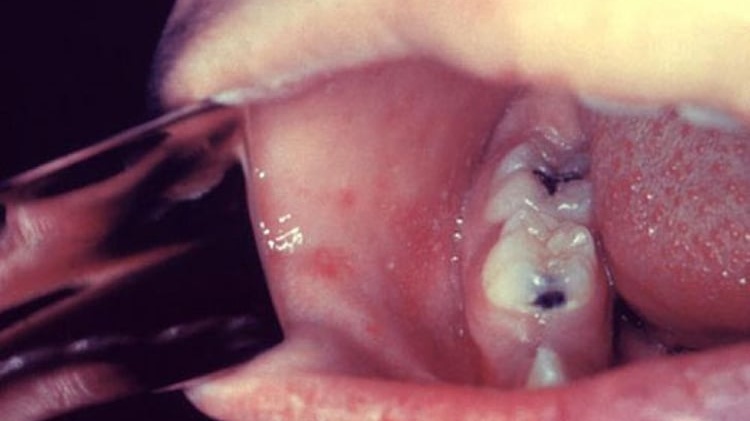

Đốm Koplik là các đốm trắng nhỏ xuất hiện trên niêm mạc má, đối diện răng hàm trên số 1-2, thường xuất hiện 2-3 ngày trước khi phát ban sởi. Đây là dấu hiệu đặc trưng, giúp nhận biết sớm bệnh sởi trước khi có triệu chứng ngoài da.

Hạt Koplik là một đặc trưng của bệnh sởi, đặc điểm nhận dạng hạt này đó là chúng thường có màu trắng hoặc hơi trắng như hạt cát, kích thước nhỏ như đầu đinh ghim. Chúng có thể xuất hiện từ vài nốt đến vài chục hay vài trăm nốt ngay tại niêm mạc má (phần phía trong miệng, ngang răng hàm).

Xung quanh các hạt Koplik ở niêm mạc má thường có sung huyết. Hạt này xuất hiện và biến mất nhanh chóng trong vòng khoảng từ 12 – 24 giờ.

Hạt Koplik thường có màu trắng, xung quanh các hạt Koplik ở niêm mạc má thường có sung huyếtSau khi hạt Koplik lặn thì sẽ diễn ra tình trạng phát ban. Đầu tiên, chỉ là những đốm nhỏ màu đỏ, ban sởi thường có dạng sần và nổi gồ lên trên bề mặt da, các nốt ban sẽ xuất hiện riêng lẻ hoặc thành từng cụm. Sau đó, ban sẽ nổi ở sau tai, trái và lan rộng ra những vùng khác trên cơ thể.